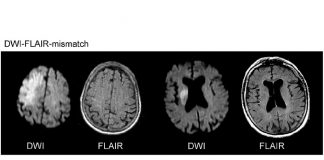

Difüzyon ağırlıklı manyetik rezonans görüntüleme, yaygın olarak akut serebral iskemide kullanılmaktadır. Genellikle kontrastsız beyin BT görüntülemesinin ardından serebral iskeminin diğer ani nörolojik fonksiyon kaybına...